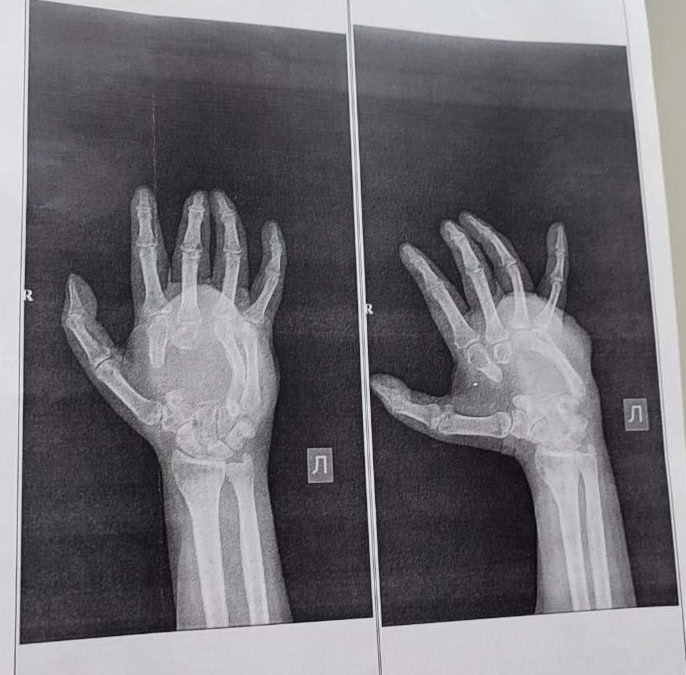

Врачи восстанавливают руку бойца СВО. Позади – костная пластика.

Как сообщил министр здравоохранения Кузбасса Андрей Тарасов, для замещения серьёзных дефектов (3 и 5 см) медики использовали собственные ткани пациента из тазовой кости.

Второй этап – вернуть подвижность и чувствительность сухожилиям и нервам.